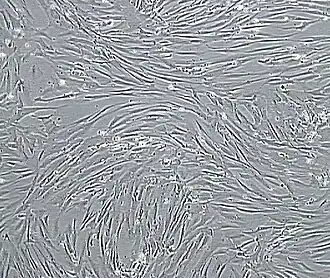

![]() Vascular smooth muscle cells, isolated from human aorta, growing and forming a monolayer in cell culture | |